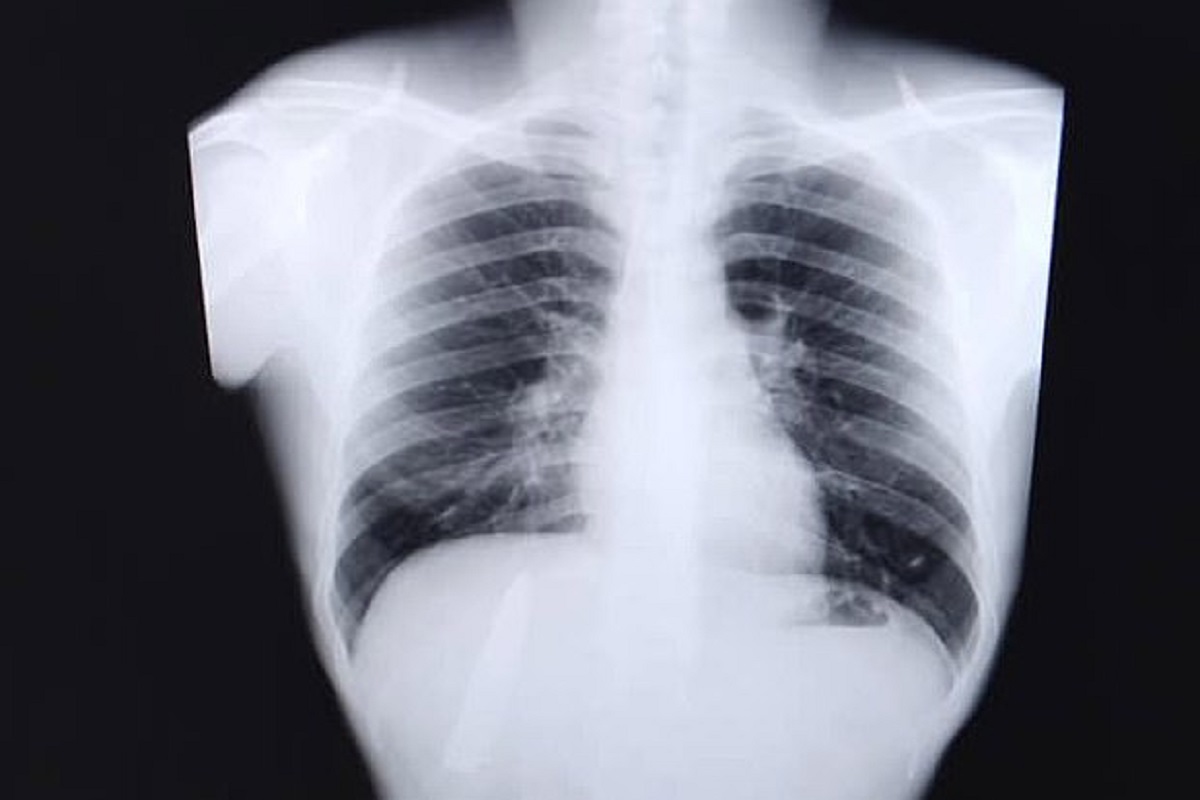

मनिला, 27 मार्च : फिलिपाइन्समध्ये (Phillipines) राहणारा 25 वर्षांचा केन्ट रेयान तोमाओन नव्या नोकरीसाठी अर्ज केला होता. या नोकरीसाठी काही वैद्यकीय रिपोर्ट हवे होते. नोकरीच्या अटीनुसार केन्ट आपली चाचणी करायला गेला. त्याने छातीचा एक्स-रे (x-ray) काढला. एक्स-रे रिपोर्ट पाहून त्याला मोठा धक्काच बसला. केन्टच्या छातीत चक्क चाकू (Knife Blade in chest) होता. 15 महिन्यांपूर्वी म्हणजे गेल्यावर्षी जानेवारीत केन्टवर चाकू हल्ला झाला होता. किदापवनमध्ये त्याच्यावर हल्ला करण्यात आला होता. तेव्हा तो गंभीर जखमी झाला होता. त्याला सार्वजनिक रुग्णालयात दाखल करण्यात आलं. डॉक्टरांनी त्याच्यावर उपचार केले. पण यानंतर केन्टला थंड वातावरणात छातीत दुखायचं. याचं कारण त्याला माहिती नव्हतं. किरकोळ वेदना असतील म्हणून त्यानेही त्याकडे फारसं लक्ष दिलं नाही. पण नव्या नोकरीसाठी म्हणून त्याने एक्स-रे काढला आणि त्याला धक्का बसला. त्याच्या छातीतील वेदनेचं नेमकं कारण समजलं. हे वाचा -

केन्टच्या छातीत चक्क चाकू होता. हा तोच चाकू आहे, ज्याने पंधरा महिन्यांपूर्वी केन्टवर हल्ला करण्यात आला होता. हा चाकू केन्टच्या शरीरात तसाच राहिला होता आणि त्यामुळेच त्याला त्रास होत होता. डॉक्टरांनी त्यावेळी जेव्हा केन्टवर उपचार केले तेव्हा त्यांनी फक्त त्याच्या जखमांना स्टिचेस घातले. त्याचा एक्स-रे काढला नव्हता. ‘माझ्या छातीत नेहमी वेदना होत होत्या. जेव्हा थंडी होती तेव्हा या वेदना तीव्र व्हायच्या पण माझ्या छातीत चाकू होता हे मला माहितीच नव्हतं’, असं तोमाओने स्थानिक मीडियाशी बोलताना सांगितलं. हे वाचा -